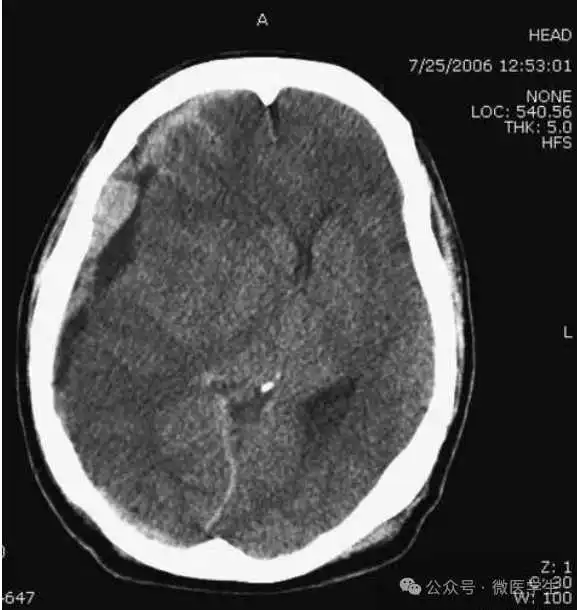

颅脑CT常用的三个窗(图A-C):

- 图C:血窗(the blood window)

图C:血窗;更利于显示硬膜下或颅内出血。

本例表现:骨窗示:右顶骨骨折;三个窗均示:软组织水肿并皮下积气;血窗:少量硬膜下血肿。